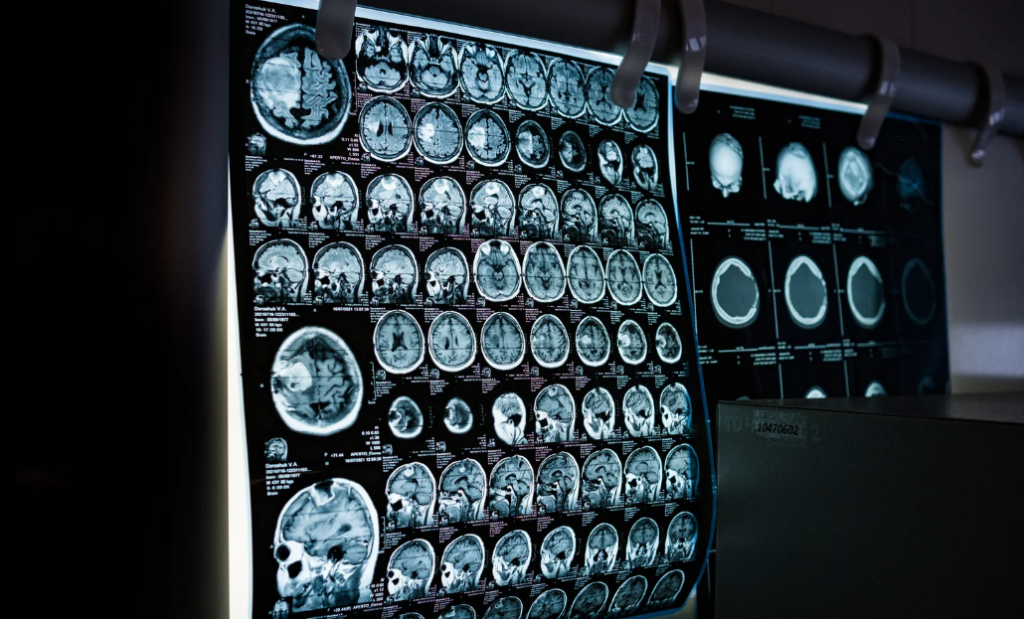

La resonancia magnética (RM) es un examen más avanzado que utiliza campos magnéticos y ondas de radio, sin radiación, para obtener imágenes muy detalladas.

Se usa sobre todo cuando el médico necesita observar tejidos blandos, como músculos, ligamentos, cerebro o médula espinal.

- Evaluación neurológica (dolores de cabeza intensos, mareos, alteraciones sensitivas).

- Estudio de tumores, inflamaciones o lesiones internas profundas.

A diferencia de la radiografía, la resonancia puede mostrar alteraciones que no se ven con otros métodos, permitiendo un diagnóstico mucho más preciso y completo.